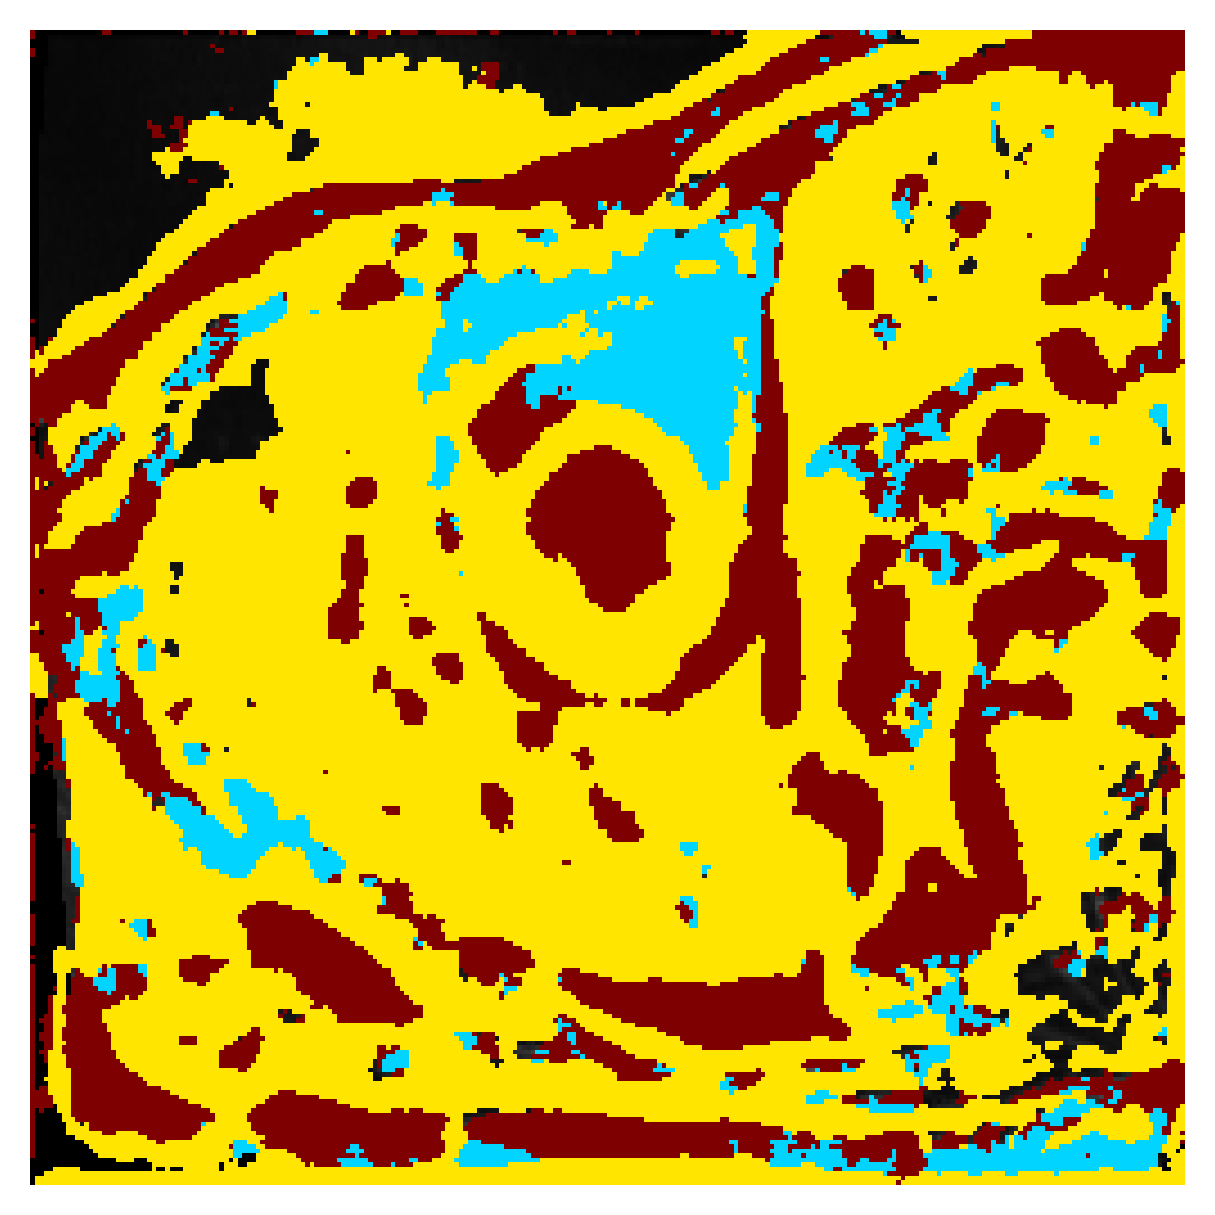

We normalize the volumes and resize the slices to pixels. As the official dataset comes with full annotations, we create a synthetic point ground truth. This is done by first randomly choosing the centers of the point annotations within the class masks, followed by filling an ellipse with axes lengths of and (in pixels) around each center. The intersections of these elliptic discs with the underlying full annotations are then used as our point ground truth. See Figure 2 for an example of the created weak annotation mask. The point annotations are created for every slice, one for each foreground object present in the slice.